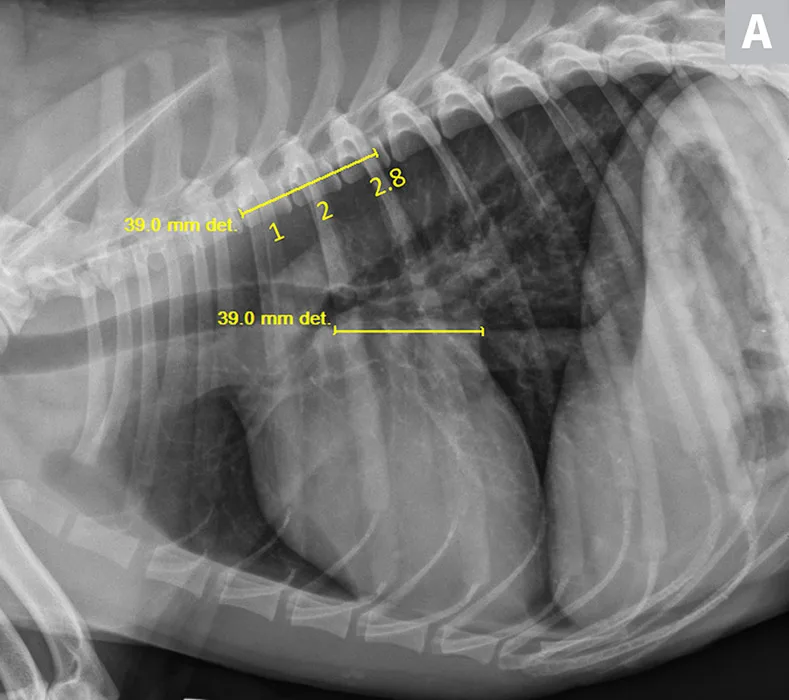

FIGURE 1

VLAS measurement in a dog with suspected stage B1 MMVD using a left lateral radiograph (A). A caliper was used to measure from the center of the most ventral aspect of the carina to the most caudal aspect of the left atrium, where it intersects with the dorsal border of the caudal vena cava. This measurement was transferred to the cranial aspect of T4 and extended caudally along the thoracic vertebrae. The number of vertebrae this line transversed was rounded to the nearest tenth to determine VLAS (2.1 VBUs). Stage B1 MMVD was confirmed via echocardiography. A redundant dorsal tracheal membrane, gastric food/foreign material, and mild T3 to T4 spondylosis deformans can also be seen. An orthogonal radiograph of the patient provides a more complete evaluation of cardiac silhouette (B); normal location of the left atrium is indicated (circle).

Thoracic radiographs revealed mild, left-sided cardiomegaly (Figure 2). VHS was 11 (normal, 9.2-10.3; >10.5 is suggestive of cardiomegaly in adult dogs14). VLAS was 2.8, suggesting left atrial enlargement. Based on physical examination and radiographic findings, stage B2 MMVD was suspected. Medical therapy and continued monitoring (ie, physical examinations, thoracic radiography) were recommended to identify worsening of the condition and possible progression to CHF.

VLAS measurement in a dog with suspected stage B2 MMVD using a right lateral radiograph (A). A caliper was used to measure from the center of the most ventral aspect of the carina to the most caudal aspect of the left atrium, where it intersects with the dorsal border of the caudal vena cava. This measurement was transferred to the cranial aspect of T4 and extended caudally along the thoracic vertebrae. The number of vertebrae this line transversed was rounded to the nearest tenth to determine VLAS (2.8 VBUs). Stage B2 MMVD was confirmed via echocardiography. Other structures are unremarkable. An orthogonal radiograph of the patient provides a more complete evaluation of cardiac silhouette (B); normal location of the left atrium is indicated (circle).